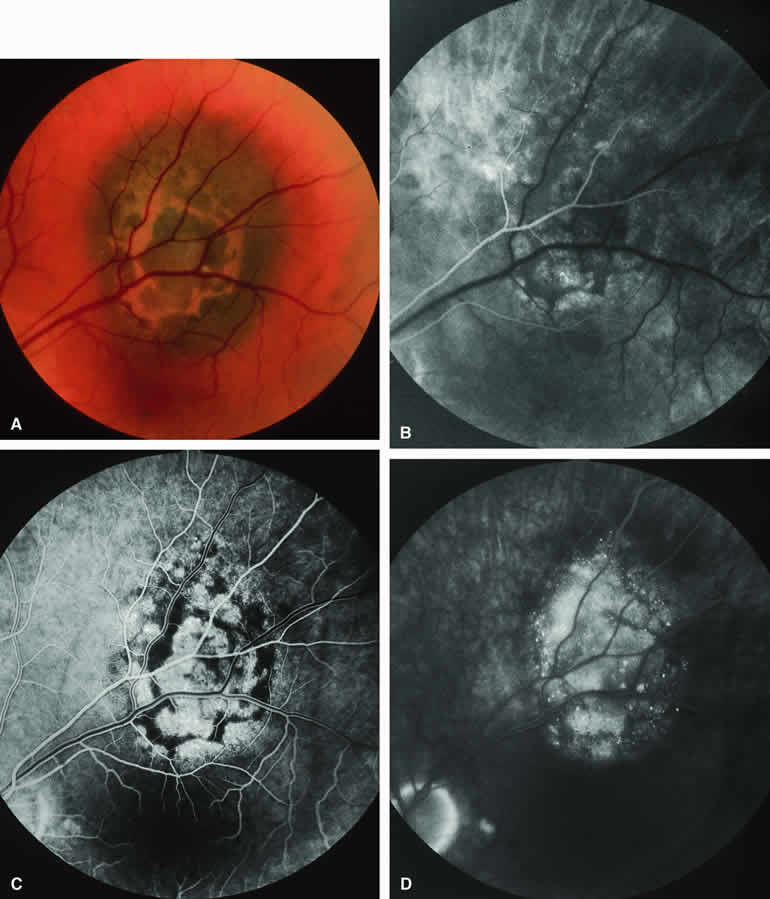

Choroidal Melanoma With Nodular Eruption Through Bruch's Membrane

If a choroidal melanoma has erupted through Bruch's membrane (Figs. 13A and 14A), it forms an apical nodule that is generally hypomelanotic and contains many large-caliber blood vessels. Fluorescein angiography of these tumors (see Fig. 13B, C, and D) typically shows hypofluorescence of the base of the lesion during the early frames, relatively rapid filling of the prominent blood vessels in the apical nodule during the venous and recirculation frames, and intense late staining of the apical nodule resulting from progressive fluorescein leakage by the late-phase frames. Similarly, ICG angiography of these tumors (see Fig. 14B, C, and D) also shows relative early hypofluorescence of the tumor base, early filling of prominent intralesional blood vessels within the apical nodule, intense staining of the apical nodule by the recirculation phase frames, and persistent late hyperfluorescence of the mass.

Fig. 13. Choroidal melanoma with nodular eruption through Bruch's membrane. A. Mushroom-shaped choroidal melanoma inferonasal to optic disc, showing dark basal region and lighter apical eruption through Bruch's membrane. Note prominence of intralesional blood vessels within apical portion of lesion. B-D. Fluorescein angiogram of lesion. B. Arterial phase frame showing fluorescence of large-caliber blood vessels within hypofluorescent apical nodule of tumor. C. Venous phase frame showing increased prominence of intralesional blood vessels, as well as alterations of retinal capillary bed where retina is thinned over apex of tumor. D. Late-phase frame showing intense hyperfluorescence of apical nodule of tumor.

Fig. 14. Choroidal melanoma with nodular eruption through Bruch's membrane. A. Amelanotic small macular choroidal tumor with amelanotic apical nodular eruption through Bruch's membrane and clumps of black retinal pigment epithelial (RPE) pigment along nasal margin of lesion.B-D. Indocyanine green (ICG) angiogram of lesion. B. Early-phase frame showing several prominent fluorescent intralesional blood vessels within apical nodule, generalized mild hypofluorescence of lesion, and choroidal fluorescence blockage by the RPE pigment clumps on the subfoveal portion of the lesion's base. C. Intermediate-phase frame showing increased fluorescence of tumor and reduced visibility of intralesional blood vessels. D. Late-phase frame showing greater hyperfluorescence of tumor base than of apical nodule and area of hypofluorescence along inferior margin of mass.